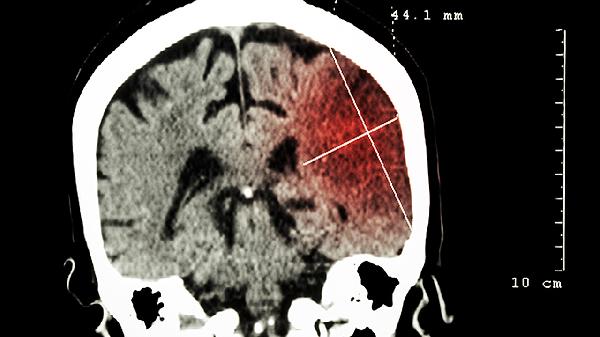

晚期脑癌能活多久?

晚期脑癌患者一般可以存活4年左右,有些症状严重的患者可能只能存活3年。一旦肿瘤增大,压迫脑干,很容易导致死亡。

Ⅲ-Ⅳ对于水平胶质瘤患者,生存周期可能只有1-3年,还有胶质母细胞瘤Ⅳ等级患者生存周期较短,平均约8个月。我很高兴为您服务,看到了您的问题。根据您的描述,如果不治疗,三个月左右可能会出现问题。